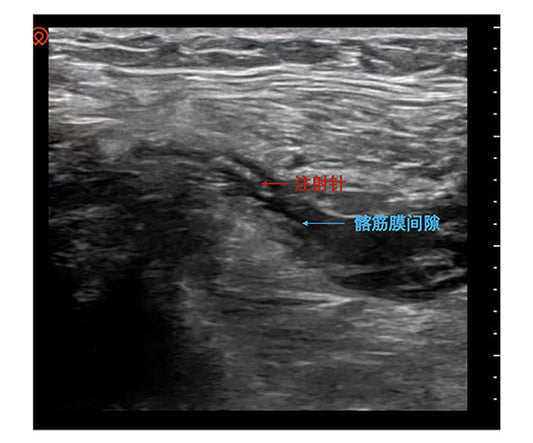

The expert team at Fuwai Hospital (Beijing) has successfully pioneered Renal Denervation (RDN) for Refractory Hypertension (RH). By utilizing radiofrequency energy to suppress hyperactive sympathetic drive, this procedure offers a...

From Pharmacological Resistance to Physical Neu...